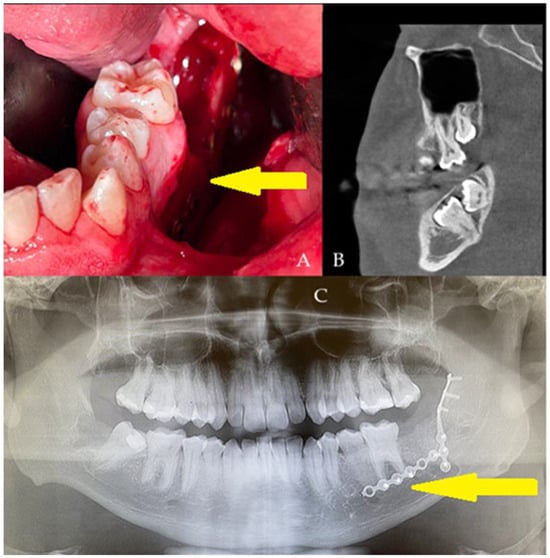

Postoperative histopathology (A) was compared with microbiological evaluation (B). The following paper illustrates a very clear radiographic–histologic mismatch in the selected case, because radiographic stability does not guarantee microbiological or histopathological healing. In connective tissue under 630× magnification with H-E staining, with differentiation for Gram-positive/-negative bacteria (1000×). Black arrows show Gram-positive bacteria. The clinical specimen obtained was subjected to microscopic examination using Gram staining. Then, it was inoculated onto blood agar (Columbia agar base agar, Oxoid Ltd., Basingstoke, UK; supplemented with 5% sheep blood), MacConkey agar (Oxoid), and Sabouraud dextrose agar (SDA, Oxoid), and incubated for 48 h at 37 °C (30 °C for SDA), under aerobic and anaerobic conditions. Grown cultures were analyzed phenotypically (colony morphology, Gram reaction, catalase activity), and chosen single colonies were subcultured under the same conditions. After obtaining pure cultures, DNA was isolated (Genomic Mini, A&A Biotechnology, Gdańsk, Poland), and the bacteria were identified by sequencing a fragment of the 16S rRNA gene, using PCR primers 16S-27f and 16S-907r. Gram-positive cocci in pairs or forming chains were observed in the preparations ((D)—direct specimen staining (top) and made of culture of S. anginosus (bottom)) from the microbiological scrub taken during the final surgery. Moderately abundant and mixed bacterial growth was detected. Three types of colonies were present in both aerobic and anaerobic cultures. Among the isolates tested via 16S rRNA gene sequencing, the two most abundant (one from aerobic and one from anaerobic culture) were recognized using the Basic Local Alignment Search Tool (https://blast.ncbi.nlm.nih.gov/Blast.cgi, accessed on 1 September 2025) as Streptococcus anginosus (100% identity with sequences listed in the GenBank database). Another three were assigned to the species Streptococcus mitis (identity 99.05–100%). The sequence of the remaining one was paired with one belonging to an uncultured bacterium, and the next best match was Streptococcus oralis (98.02%). All the isolated bacteria are regarded as commensals inhabiting, among others, the oral cavity. These microorganisms; however, under certain conditions, are able to cause opportunistic infections. Additional histochemical test revealed the presence of Gram-positive bacteria, which were inducing a mild immune response, associated with activation of the macrophage–lymphocyte system, as well as the presence of neutrophils. Inflammation appears to be essential for wound healing, with no evidence of bone resorption, granulation tissue, or inflammatory bone infiltration. Gram staining revealed no bacteria in the bones; they were present only in the adjacent tissues. The bacterial infection was not associated with the allograft. In relation to the above, no changes were observed in the radiological image of the bone (Figure 3B,C). Wound healing after debridement was uneventful (B,C). Because of the changes in microbiological scrubs from the wound, the patient continued intraoral antibiotics consisting of Amoxiclav Quick Tab (Amoxicillinum, Acidum clavulanicum, 2 × 1 g—Sandoz Poland, Warsaw, Poland) after the surgery for seven days. The following case presents how bone healing in early stages up to six months does not correspond with clinical, radiological, and microbiological findings. This might be found because of a very local and small wound without any progression and invasion of deep layers of grafted FFABG bone in both clinical and radiological examination. The disproportion between clinical and radiological appearance when comparing the healing is not equal to the bone healing in gathered histopathological samples, nor is it free of bacterial colonies, regardless of the pharmacological agents used. Histopathological examination revealed parts of healed bone surrounded by unhealed necrotic bone, surrounded by cyst-like thin-layer pathologies with bacteria scattered along the different layers of the sample. It seems that the role of saliva, oral biofilm, and adjacent local oral factors has a great effect on the bone. Secondly, and possibly, bacterial influence on the FFABG is higher when the bone is exposed to the oral cavity and not covered by a flap. The mixture of neutrophile, macrophage, and lymphocytic specimens suggests an unspecified inflammation with some swelling and cyst-like mass when the deeper layer was fully healed (hard bleeding bone with full remodeling evaluated during revision surgery). The presented process suggests that the wound and the patient’s body tried to get rid of and remove the entire unhealed bone on their own and decrease any potential unwanted results on their own. The presence of a connective tissue capsule surrounding a radiologically healthy bone was not seen in the panx radiograph. In radiological images, the bone was healing properly, but in microscopic evaluation, the superficial layer of bone was not healing and was not fully remodeling in the mentioned six-month time frame. Radiological evaluation did not reveal any granulation tissue, empty cystic-like cavities, bone resorption, or any worrisome radiological symptoms. Radiology alone is not sufficient to establish bone healing, bone remodeling, and possible bone infection with bacteria in its early stages, when the patient’s local or general symptoms do not reflect any active inflammation, granulation tissue, or pus formation in clinical examination [6,7]. Any early inflammation processes in the used FFABG are difficult to establish in any early radiological detection. Based on the histopathological evaluation, any late stages can be more successfully identified in routine panx, as presented in a comparable case (Figure 3C). Local bone swelling with inflammatory reaction is normally visible more accurately in early radiographs. Perhaps due to the extensive usage of local agents and antibiotics for specific microflora, the scope of infection and bone changes was limited to a very small portion of bone that could not be evaluated and established in such early stages of healing. When some troublesome or worrisome radiological (panx) or clinical symptoms arise, improved diagnostics with CBCT should assess the bone healing and remodeling more accurately if there is a necessity for such a step. Secondly, wound dehiscence might happen in each stage of healing and the surgery period, but as it seems in this case, local wound care and local appliances might have improved the final outcome [8,9,10]. Based on the following cases, the authors recommend that (1) each allogeneic bone should be closely monitored; (2) a potential need for combined imaging and microbiological surveillance should be considered in wound dehiscence and lack or prolonged healing; (3) any sole reliance on panoramic radiography alone should be limited; (4) each individual patient case improved oral hygiene protocol before and after surgery helps in decreasing possible worrisome healing; (5) microbiological scrubs help a lot in wound treatment in the oral cavity.